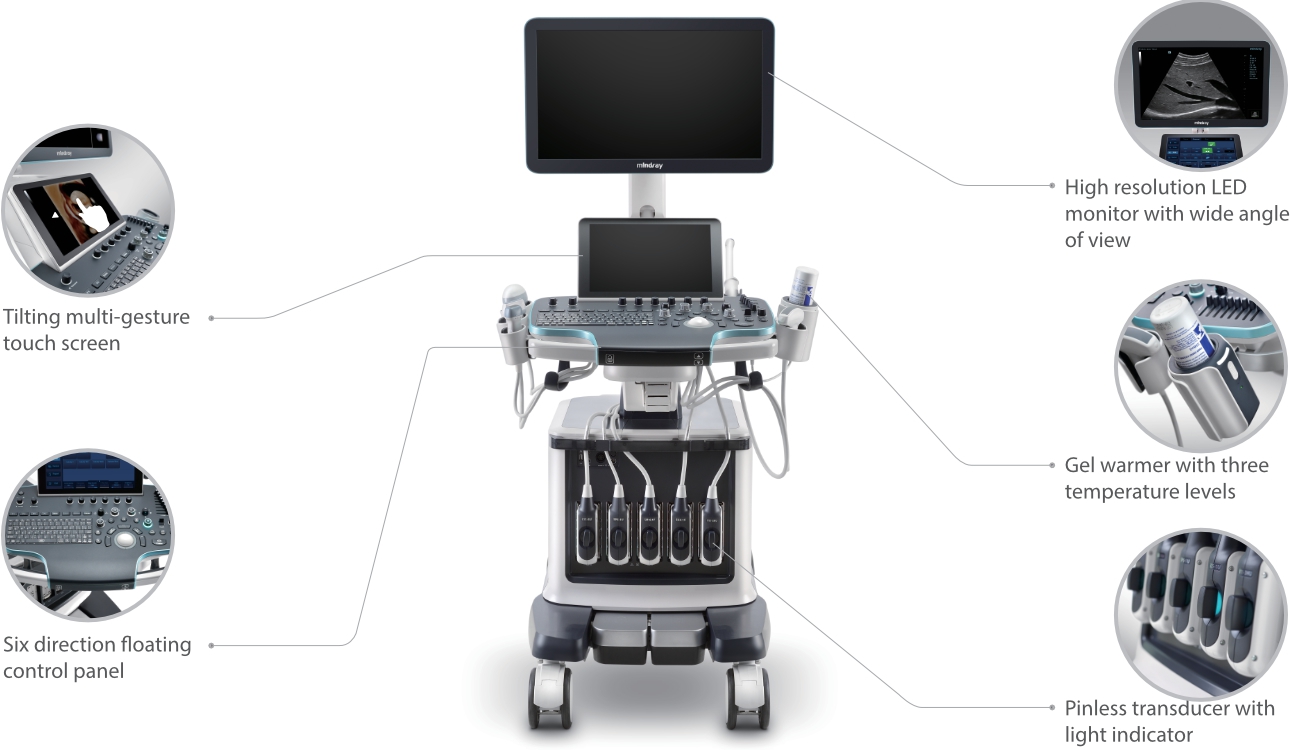

Resona 7

Novedades en la innovación de ecografías

con Zone?Intelligence

Desde que se fundó la compa?ía, Mindray ha explorado incansablemente nuevas formas de mejorar la confiabilidad del diagnóstico. Con la revolucionaria tecnología de ZONE Sonography?, la nueva plataforma ZST+ de Resona?7 lleva la calidad de la imagen por ecografía a un nivel superior mediante el procesamiento de datos de canal y la adquisición de zona.

Además de la calidad de imagen de primer nivel, Resona?7 también mejora las capacidades de investigación clínica con el revolucionario V?Flow para la evaluación hemodinámica vascular y con la adquisición de planos más inteligente a partir de conjuntos de datos 3D para el diagnóstico del SNC fetal. Al combinar el funcionamiento multitáctil basado en gestos más intuitivo y todas las características clínicas esenciales, Resona?7 realmente lidera las novedades en innovación de ecografías.